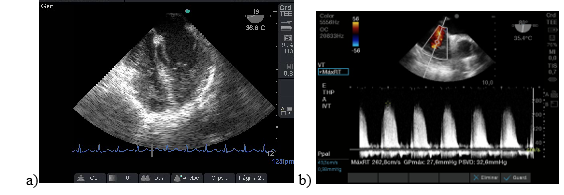

Paciente de 26 años que se realizó trasplante hepático con donante vivo con antecedentes de colitis ulcerosa y colangitis esclerosante y desnutrición. El ETE realizado luego del desclampeo reveló insuficiencia cardíaca derecha, ventrículo derecho aumentado de tamaño e hipertensión pulmonar. Figura 7: a y b